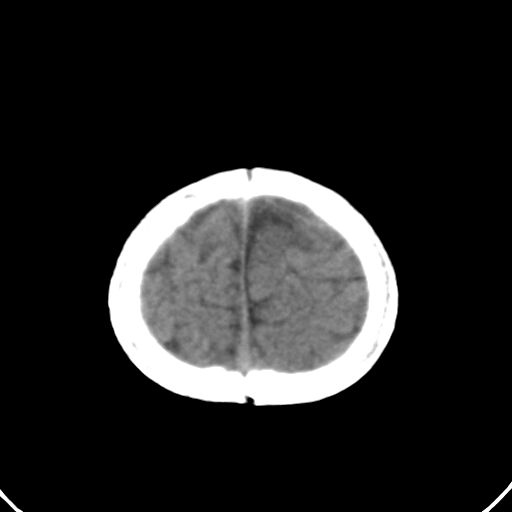

男,10月,足月剖腹产,无缺氧病史,当时评分均正常,学走路时脚后跟不着地!

小孩子片子,看得少,请各位老师看看有问题没?

未见明显异常。

外部性脑积水

考虑外部性脑积水

轻度脑外脑积水表现.